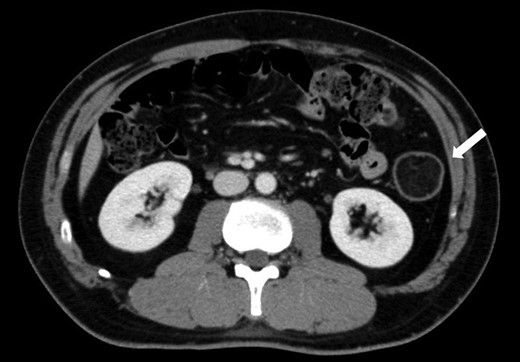

A 43-year-old man presented to the emergency department with the sudden onset of massive hematochezia. Rectal examination revealed hematochezia, but was negative for hemorrhoids. Laboratory findings were normal except for mild anemia. The patient was admitted for further examination. A submucosal tumor with a reddish surface, measuring 5 cm in diameter, without active bleeding was found on colonoscopy in the descending colon (Fig. 1a). The mucosa surrounding the tumor, especially on the contralateral wall, had mucosal hematoma (Fig. 1b). Biopsy specimens taken from the tumor exhibited only inflammatory tissue. Contrast-enhanced computed tomography (CT) demonstrated a solid mass with fat density of 5 cm in diameter in the descending colon (Fig. 2). The possibility of re-bleeding and malignancy could not be eliminated, and laparoscopic left hemicolectomy was planned.

CT findings at the time of diagnosis: contrast-enhanced CT of the abdomen at the time of diagnosis revealed a solid mass measuring 5 cm in diameter with fat density in the descending colon (white arrow).